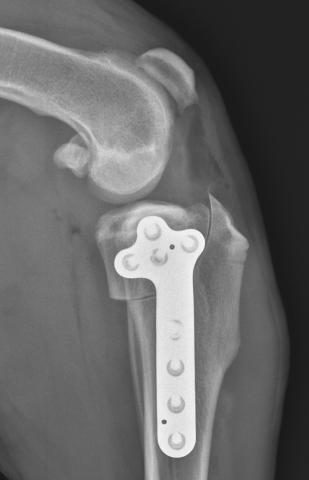

Operace kolenního kloubu psa u přetrženého zkříženého vazu

Přesto, že metoda stabilizace kolenního kloubu po ruptuře předního zkříženého vazu TPLO byla zavedena Barclayem Slocumem již v roce 1993, prožívá v posledních letech obrození.